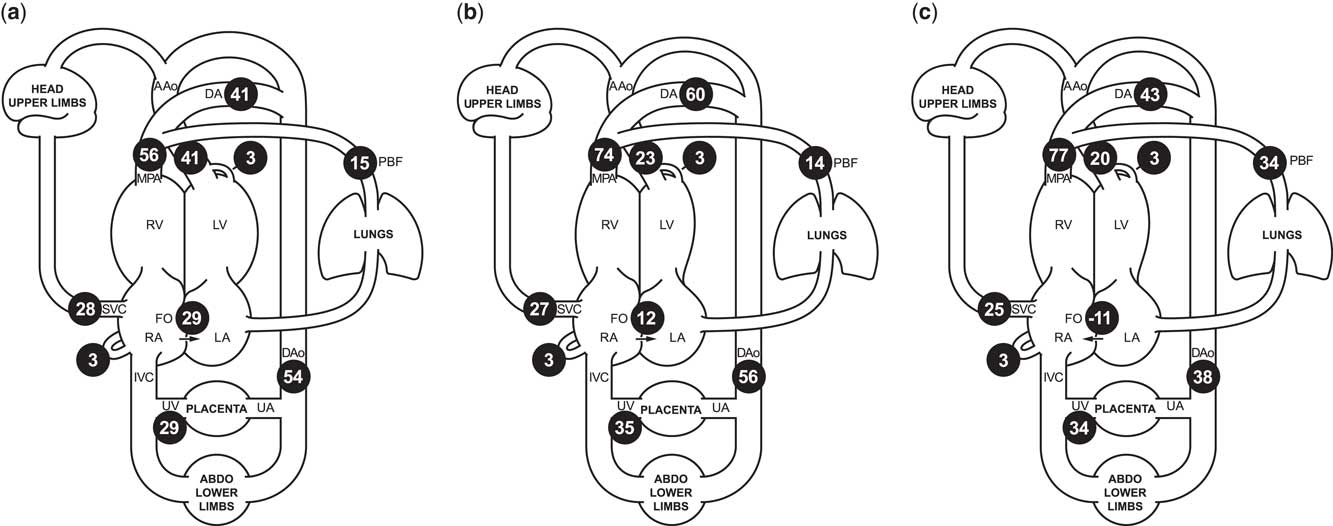

Figure 1 Cardiac MRI flow distribution in the foetal circulation, shown as mean percentages of the combined ventricular output (CVO) in ( a ) 40 normal late gestation foetuses, and ( b ) our case of borderline left ventricular hypoplasia, before maternal hyperoxygenation, and ( c ) following 20 minutes of maternal hyperoxygenation with 70% oxygen by non-rebreathing mask. Foramen ovale shunt is calculated as the difference between the ascending aorta and pulmonary blood flow. The reported mean percentages of the distribution of CVO required minimal adjustment to conform to a principle of conservation of flow across the foetal circulation, using a published model extrapolated from measured flows using constrained non-linear optimisationReference Prsa, Sun and van Amerom 7 . AAo/Dao=ascending/descending aorta; DA=ductus arteriosus; FO=foramen ovale; MPA=main pulmonary artery; PBF=pulmonary blood flow; RA/LA=right/left atrium; RV/LV=right/left ventricle; SVC/IVC=superior/inferior vena cava; UA/UV=umbilical artery/vein.

We present a case of borderline left ventricular hypoplasia diagnosed in foetal life. Foetal echocardiography showed significant ventricular disproportion, mitral valve diameter 6 SDs below the mean, and restrictive right-to-left flow at the oval foramen. The ascending aorta was small, and colour imaging revealed that a proportion of the blood supply to the upper body was being supplied by the right ventricle via the arterial duct, with retrograde flow across the aortic isthmus. Foetal cardiac MRI at 37 weeks’ gestation also showed ventricular disproportion (Supplementary Figures S1 and S2). Blood flow measurements made using cine phase-contrast imaging with metric optimised gatingReference Seed, van Amerom and Yoo 5 revealed a 50% reduction in ascending aortic flow compared with normal controls, with a 3:1 ratio of right ventricular to left ventricular output (normal 1.3:1). Pulmonary blood flow was normal. Oval foramen flow was significantly lower than the normal foetal mean (Fig 1), consistent with possible flow restriction across the atrial septum.

We hypothesised that maternal hyperoxygenation would induce pulmonary vasodilationReference Rudolph 8 and increase filling of the left ventricle. However, whereas maternal hyperoxygenation (20 minutes of 70% oxygen by non-rebreathing mask) caused a nearly twofold increase in pulmonary blood flow by MRI (Fig 1), the increased venous return did not augment the ascending aortic outflow. Instead, there was a reversal of atrial shunting, suggesting that valvar obstruction and ventricular hypoplasia were restricting flow across the left heart.